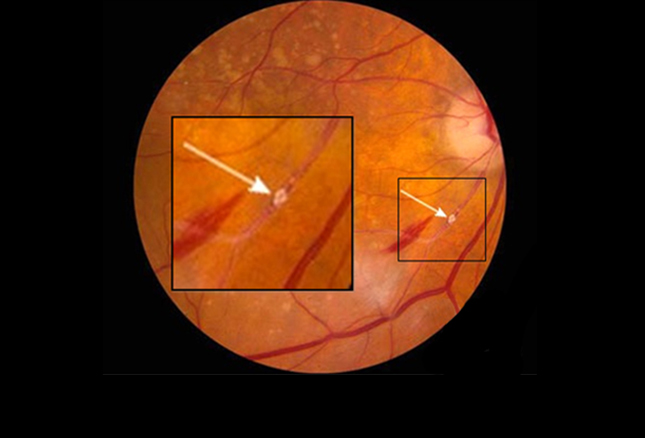

视网膜异常:14种全身性疾病的征象(二)